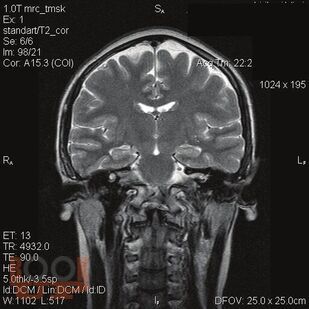

В монографии рассматриваются особенности проявления и методы диагностики когнитивной дисфункции у пациентов с сахарным диабетом 1 типа. Описан комплекс современных методов исследования и диагностики когнитивных нарушений при сахарном диабете 1 типа. Систематизированы сведения в отношении влияния когнитивной дисфункции на качество жизни пациентов с сахарным диабетом 1 типа. Представлен алгоритм ведения диспансерных пациентов с сахарным диабетом 1 типа в плане диагностики когнитивной дисфункции.

В монографии рассматриваются особенности проявления и методы диагностики когнитивной дисфункции у пациентов с сахарным диабетом 1 типа. Описан комплекс современных методов исследования и диагностики когнитивных нарушений при сахарном диабете 1 типа. Систематизированы сведения в отношении влияния когнитивной дисфункции на качество жизни пациентов с сахарным диабетом 1 типа. Представлен алгоритм ведения диспансерных пациентов с сахарным диабетом 1 типа в плане диагностики когнитивной дисфункции. Книга адресована студентам, ординаторам, преподавателям, врачам-эндокринологам, неврологам, терапевтам.